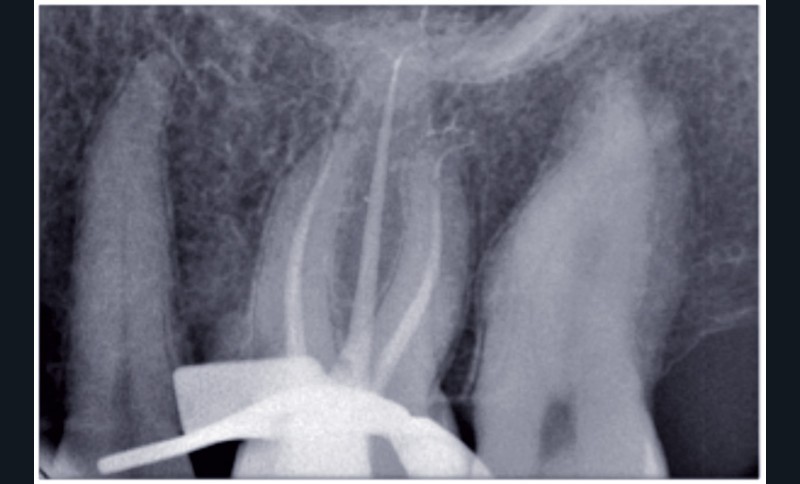

La radiographie rétroalvéolaire peut se retrouver dans ces trois cas de figure.

3. Acte complémentaire d’une endodontie (forfait)

La CCAM prévoit un dispositif spécifique de facturation des radiographies réalisées au cours d’un traitement endodontique. Ces radiographies bénéficient d’honoraires forfaitaires et peuvent correspondre

à l’un des deux actes complémentaires suivants :

• Deux radiographies rétroalvéolaires sont effectuées

au cours du traitement endodontique : l’acte a pour code HBQK040 et pour libellé « Radiographies intrabuccales rétroalvéolaires sur un secteur de 1 à 3 dents contiguës préinterventionnelle ou perinterventionnelle avec radiographie finale pour acte thérapeutique endodontique ».

Les honoraires forfaitaires sont de 11,97 €.

• Trois radiographies rétroalvéolaires sont effectuées au cours du traitement endodontique : l’acte a pour code HBQK303 et pour libellé « Radiographies intrabuccales rétroalvéolaires sur un secteur de 1 à 3 dents contiguës préinterventionnelle, perinterventionnelle et finale pour acte thérapeutique endodontique ». Les honoraires forfaitaires sont de 15,96 €.

Dans les deux cas de figure, les dates des radiographies n’ont pas d’incidence sur le « tarif forfaitaire ». Ces radiographies peuvent être réalisées dans plusieurs séances (cas de la reprise du traitement endodontique, par exemple). Les honoraires restent ceux fixés forfaitairement.

Recommandations de bonne pratique et nombre de radiographies

Les données de la littérature professionnelle, tout comme la recommandation de la HAS (novembre 2008), conseillent de réaliser, au moins, trois radiographies pour un traitement endodontique. Même en utilisant un localisateur d’apex, la radiographie per-opératoire est essentielle pour doubler la mesure électronique par une mesure visuelle, broches en place.

Le « forfait deux radiographies » prévu par la CCAM est donc d’utilisation exceptionnelle.

La plupart du temps, l’acte d’endodontie est associé au « forfait trois radiographies ».